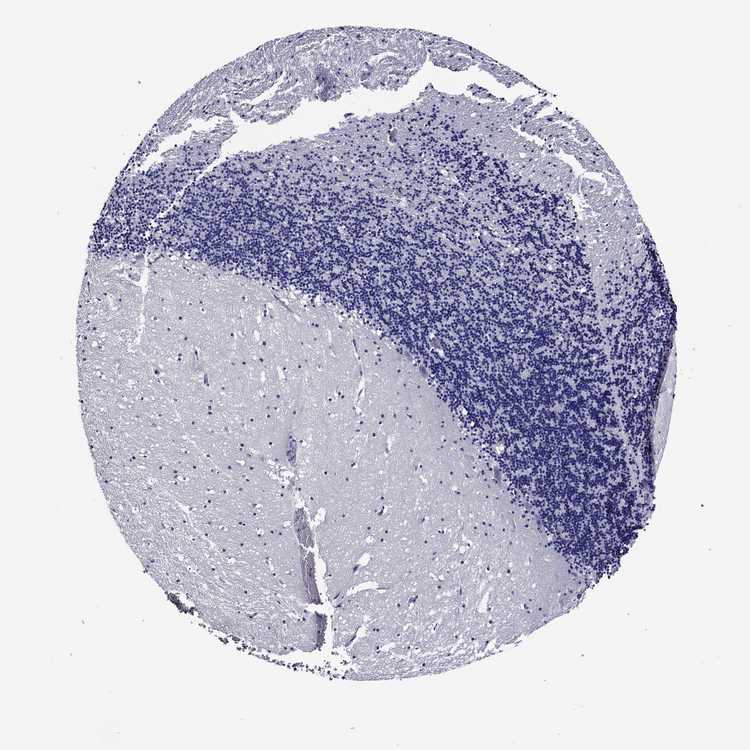

BRAIN CEREBELLUM Show tissue menu

CEREBELLUM - Expression summary

Protein expression

Cerebellumi

On the top, protein expression in current human tissue, based on all annotated cell types, is reported with the units not detected (n), low (l), medium (m) and high (h). Underneath, protein expression in each annotated cell type are reported using the same units.

Protein expression data is based on knowledge-based annotation. For genes where more than one antibody has been used, a collective score is set.

If knowledge-based annotation could not be performed for a gene, no data is displayed here. View antibody staining data further down this page.

Cells in granular layer: Low

Cells in molecular layer: Medium

Purkinje cells: Not detected

CEREBELLUM - Antibody stainingi

Antibody staining in the annotated cell types in the current human tissue is reported as not detected, low, medium, or high, based on conventional immunohistochemistry profiling in selected tissues. This score is based on the combination of the staining intensity and fraction of stained cells.

Each image is clickable and will lead to virtual microscopy that enables deeper exploration of all samples and also displays staining intensity scores, fraction scores and subcellular localization as well as patient and tissue information for each sample.

Antibody HPA035103Antibody HPA063539

Purkinje cells Not detectedNot detected

Cells in granular layer Not detectedLow

Cells in molecular layer Not detectedMedium